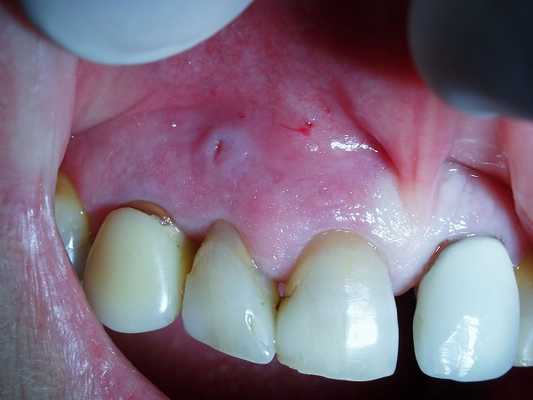

Цистотомия

Операция проводится под местной анестезией по следующей схеме: хирург выкраивает полуовальный слизисто-надкостничный лоскут в проекции кистозного образования, обнажает костную стенку и проводит трепанацию, после чего полость кисты промывается и заполняется тампоном с йодоформом. Для профилактики рецидива в ходе операции рекомендуется произвести тщательную ревизию тканей и удалить некротизированные участки. Через 7 дней необходимо сменить тампон и в дальнейшем производить смену повязки 3-4 раза. Данное вмешательство хорошо переносится пациентами, но сопровождается длительным существованием послеоперационного дефекта.

Цистэктомия

При цистэктомии киста удаляется целиком посредством отделения ее фиброзной оболочки от прилегающих тканей. Далее производится тампонада полости или сближение краев поврежденной в ходе операции слизистой оболочки. Данная манипуляция рекомендуется для пациентов с небольшими кистами либо крупными образованиями в зоне отсутствия зубов при сохранении достаточно толстого слоя костной ткани. В ряде случаев хирурги считают целесообразным объединить оба оперативных вмешательства. В послеоперационном периоде нужно внимательно следить за состоянием полости рта, использовать антисептические средства для полоскания и тщательно проводить гигиенические процедуры. При повышении температуры и наличии симптомов интоксикации необходимо как можно скорее обратиться к стоматологу-хирургу.